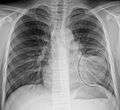

AP CXR showing left lower lobe pneumonia associated with a small left sided pleural effusion

Right upper lobe pneumonia as marked by the circle.- Left upper lobe pneumonia with a small pleural effusion.